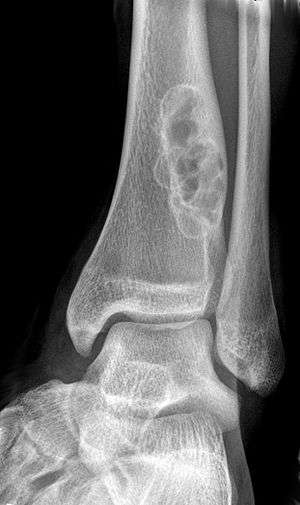

| X-ray of nonossifying fibroma of distal tibia. | |

A nonossifying fibroma (also called fibroxanthoma) is a fibrous bone lesion that is usually asymptomatic and discovered as an incidental finding on x-ray. It is the most common benign bone tumor in children and adolescents. However, it is controversial whether it represents a true neoplasm or rather a developmental disorder of growing bone. Radiographically, the tumor presents as a well marginated radiolucent lesion, with a distinct multilocular appearance. These foci consist of collagen rich connective tissue, fibroblasts, histiocytes and osteoclasts. They originate from the growth plate, and are located in adjacent parts of the metaphysis and diaphysis of long bones, most often of the legs. No treatment is needed in asymptomatic patients and spontaneous remission with replacement by bone tissue is to be expected.